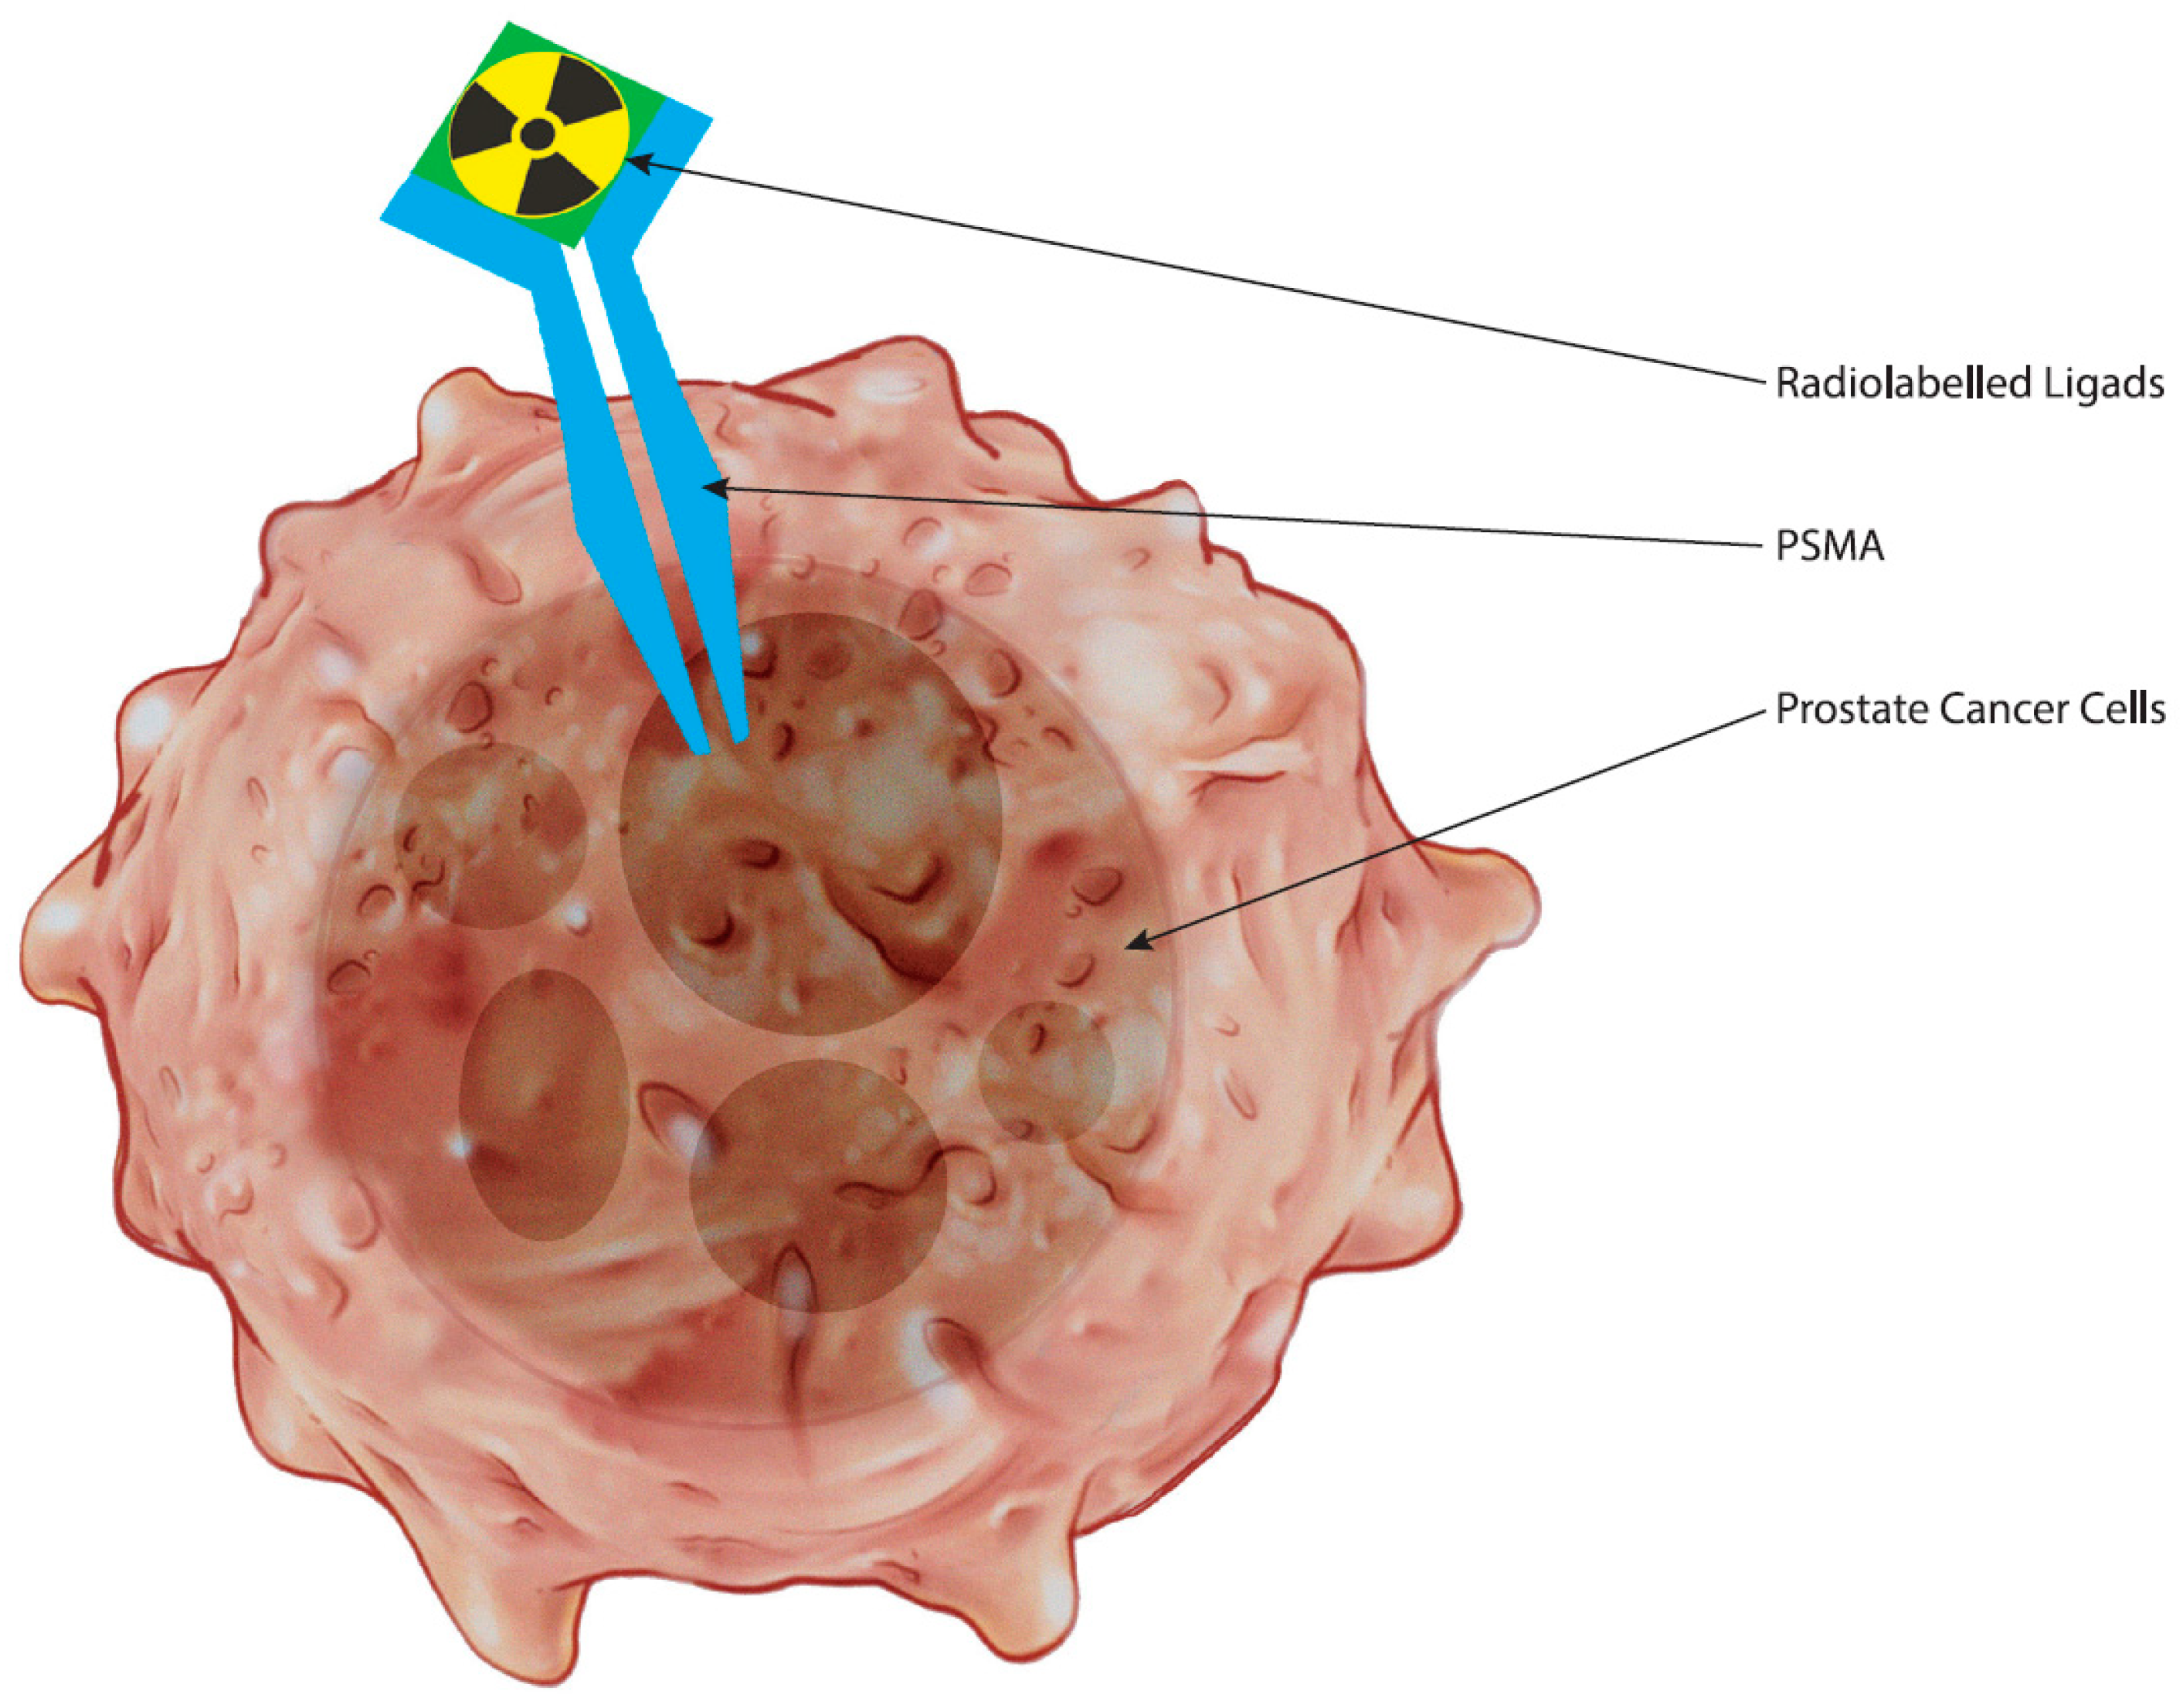

2. The Biological Underpinnings of PSMA as a Target in Prostate Cancer

3. Advances in PET-PSMA Imaging Technologies and Methodologies